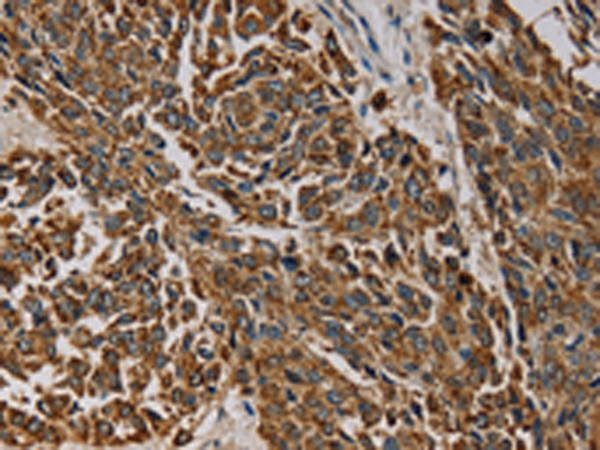

分类: 科研抗体货号: P08511别名: NYD-sp9应用: IHC反应种属: Human, Mouse, Rat